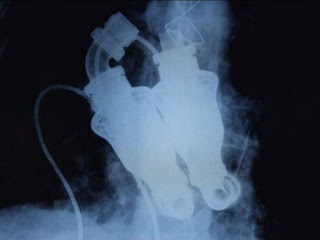

El hombre sin corazón y sin pulso: Jakub Halik

Jakub Halik es el primer hombre en conseguirlo. El suyo tenía un tumor maligno y fue sustituido por dos bombas sin válvulas cardíacas que hace que no tenga pulso sensible

El paciente, un bombero de 37 años, tenía un tumor maligno en el corazón, y la única alternativa que se le ofrecía en lugar de un trasplante inmediato era la implantación de las bombas, una que manda la sangre por la aorta, y la otra a los pulmones. "Está contraindicado hacer un trasplante cuando hay en el corazón un tumor maligno, porque los medicamentos para evitar el rechazo de un órgano extraño apoyan el proceso tumoral de las células", explicó Jan Pirk, el cardiólogo que ha realizado la intervención y candidato al galardón Cabeza checa, el más prestigioso en la esfera de la ciencia y la tecnología en el país centroeuropeo.

Halik fue operado el 3 de marzo, en una intervención que duró más de siete horas. Antes que él, esta novedosa técnica sólo se había practicado a un hombre de Texas, Estados Unidos, que sin embargo falleció poco después. El equipo médico considerará exitosa la operación "si el tumor no se extiende y si el paciente sobrevive hasta que le hagamos un trasplante de corazón", declaró Pirk. "Por eso debemos esperar todavía entre seis y nueve meses", precisó el cardiólogo del Instituto de Medicina Clínica y Experimental de Praga (IKEM).

"El paciente no tiene pulso sensible. Se creía que sin esto no se puede vivir, y se ha mostrado que sí se puede vivir sin pulso", afirma Pirk con visible orgullo. Lo más complicado fue fijar la presión de bombeo de cada uno de los dispositivos, pues la sangre que va a los pulmones debe tener menor presión para que éstos no se irriten. El único inconveniente es cargar con las pilas bajo los brazos, "al igual que James Bond lleva las pistolas", bromea el cirujano, que se ha convertido en una estrella mediática en su país.

Los acumuladores no se ven, no pesan mucho y duran entre 8 y 12 horas, mientras que el equipo regulador se lleva como una riñonera. En el caso de Halik, las revoluciones están fijadas para una actividad normal, no para correr, hacer deporte ni subir por una escalera. "No es capaz de reaccionar al esfuerzo", aseveró Pirk. Los primeros intentos de bomba artificial colocada fuera del cuerpo para apoyar al corazón durante cortos períodos de tiempo datan de la Segunda Guerra Mundial y se utilizan desde 1953.

La calidad de vida tras la operación tiene una limitación: "No pueden nadar, sólo ducharse. Pueden jugar al golf, o al ajedrez, pero seguro que no pueden correr un maratón", explica el médico. El costo se eleva a los 80 mil euros por unidad, a lo que hay que agregar los gastos de la operación, lo que deja toda la intervención en unos 250 mil euros. Esta cantidad es, a pesar de todo, bastante más asequible que la que supone implantar un corazón artificial, y además este sistema debería tener, según el experto, una vida útil mucho mayor.

Cuando la bomba se utiliza como apoyo del ventrículo izquierdo -es decir, sin que extirpe todo el corazón- hay pacientes que viven con ella al menos siete años. Son ya cien los dispositivos que, desde el año 2003, se han implantado en el prestigioso instituto médico praguense.